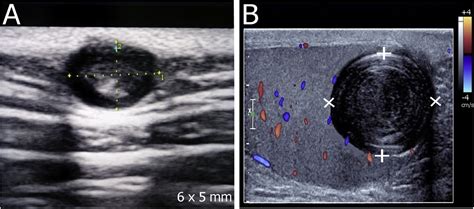

When you visit a doctor for a cyst on scrotum, they will perform a physical examination to feel the size, texture, and location of the lump. They may use a technique called transillumination, where a bright light is shone through the scrotum. Cysts filled with clear fluid will often allow light to pass through, whereas solid masses (which require more investigation) will block the light.

If the physical exam is inconclusive, the physician may order an ultrasound. A scrotal ultrasound is a non-invasive, painless imaging test that provides a clear view of the internal structures of the scrotum, allowing the doctor to definitively distinguish between a benign cyst and other potential issues.